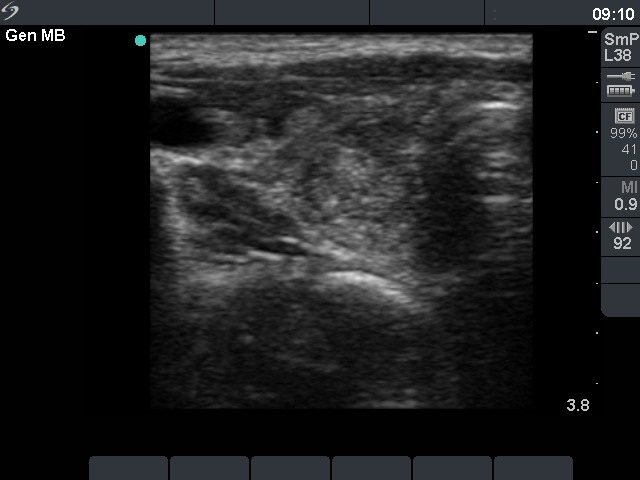

Benign hyperplastic nodules (histological diagnosis) - case cons 024 |

The larger lesion has a solitary bright figure which shape stands for a comet-tail artifact.

There are pale lines and granules within the nodule - these figures correspond to a connective tissue. The three granules are probably also presentations of a connective tissue.